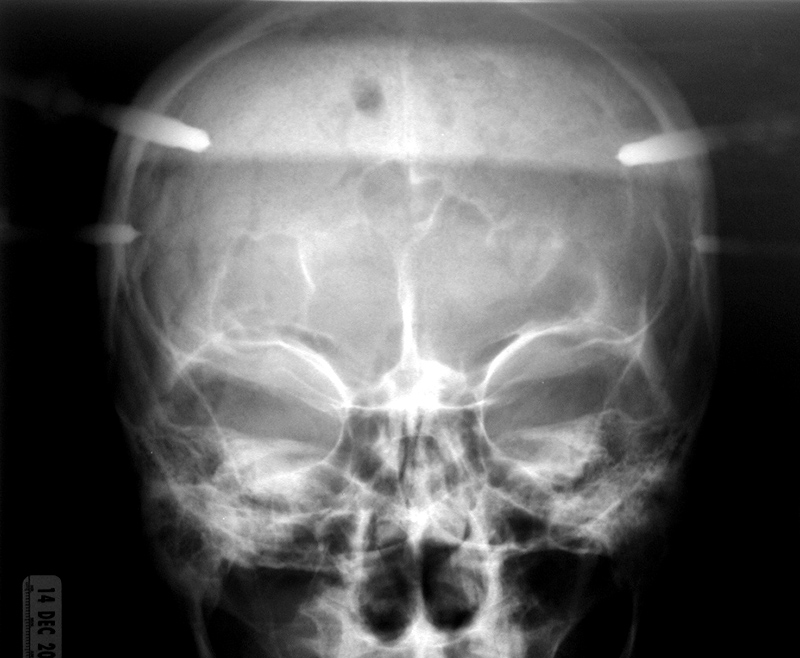

| Child with severe intracranial and cervical spine injuries with bilateral cranial stabilization tongs, an endotracheal tube, an oroogastric tube, and a feeding tube entering via the nose. From Hunter, 2004 |

Cranial (head) tongs are used to stabilize the head and neck in a patient with a cervical spine fracture. One or more screws penetrate the outer table of the skull on each side. They are connected to each other by horizontal or vertical bars on each side that are attached to an external traction device. From Hunter, 2004 |